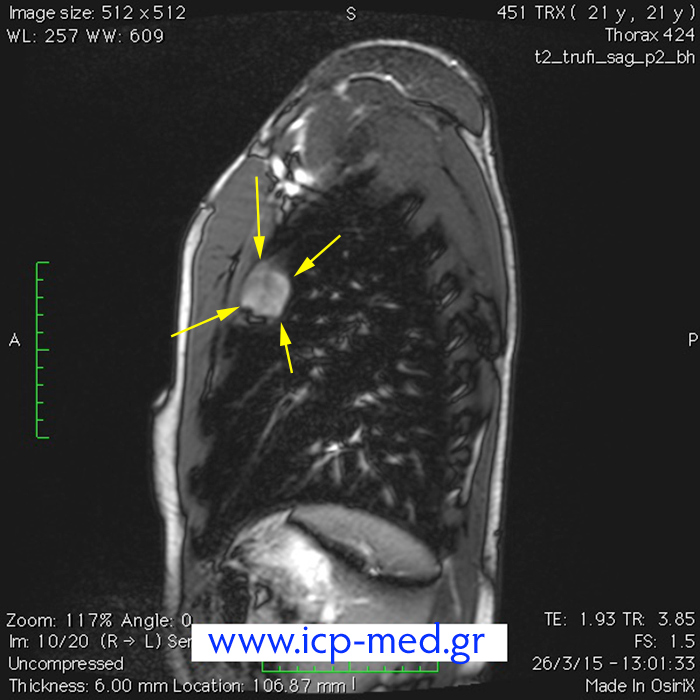

8. Preop MRI scan (sagittal view)